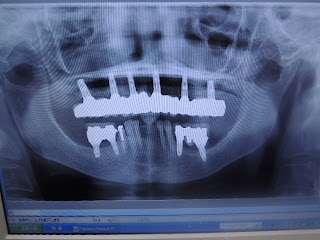

今日の午前中はCTによるTMDの撮影から、側頭骨関節窩と下顎骨下顎頭の偏位を適正骨関節隙を基準に数値化し、明確な誘導の方向と量を定めて顎誘導をするという、JPI手法に基づいた技工をしていました。

既に上下臼歯部は全てTEKに置き換わっていることや、これまでの他院での治療などが原因で最低限の侵襲でということで、シェルタイプで誘導することになりました。